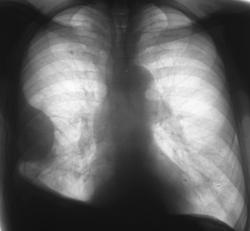

Рентгенологическое исследование проведено на рентгенодиагностическом аппарате на 3 рабочих места «Вироматик» методами рентгенотелевидения и рентгенографии. При рентгенотелевидении скиалогическая картина по сравнению с картиной, полученной при флюорографическом исследовании не меняется. При исследовании на латероскопе и трохоскопе растекания жидкости не зафиксировано. Изменения формы «паракостальной» фокусной тени и затемнения над правым куполом диафрагмы не зафиксировано, что косвенным образом свидетельствует о наличии мощных шварт.

На иллюстрациях 4 и 5 – рентгенограмма и фрагмент с увеличением визуализируется типичная теневая картина паракостально-наддиафрагмального осумкованного плеврита.